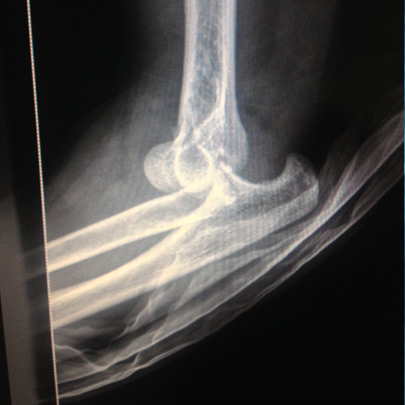

Fracturas y luxaciones

Cirugía de codo